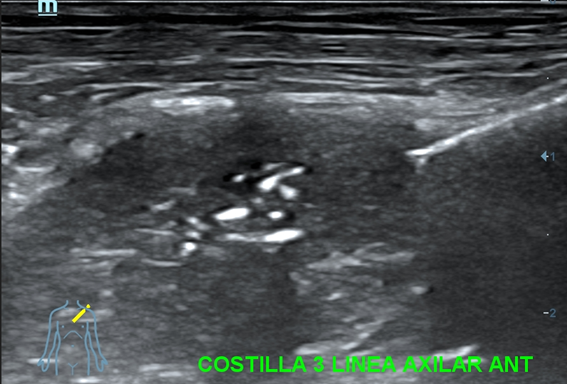

Se decide completar la exploración con ecografía clínica de las costillas afectadas.

Eco clínica costal: en 3ª y 4ª costillas izquierdas, a nivel de línea axilar anterior, se visualiza lesión que rompe y destruye la cortical infiltrando partes blandas. Hipervascularización con Doppler color.